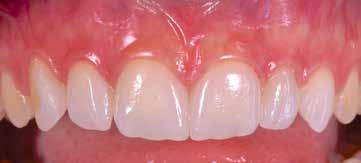

B.M. Bambina di sei anni e mezzo, con malocclusione scheletrica di II Classe, deep-bite over-jet elevato, lieve contrazione dell’arcata superiore, alterazione dell’eruzione dell’elemento dentale 21.

Fig. 122 > Immagine intraorale frontale.

Fig. 15 > Immagine intraorale frontale.